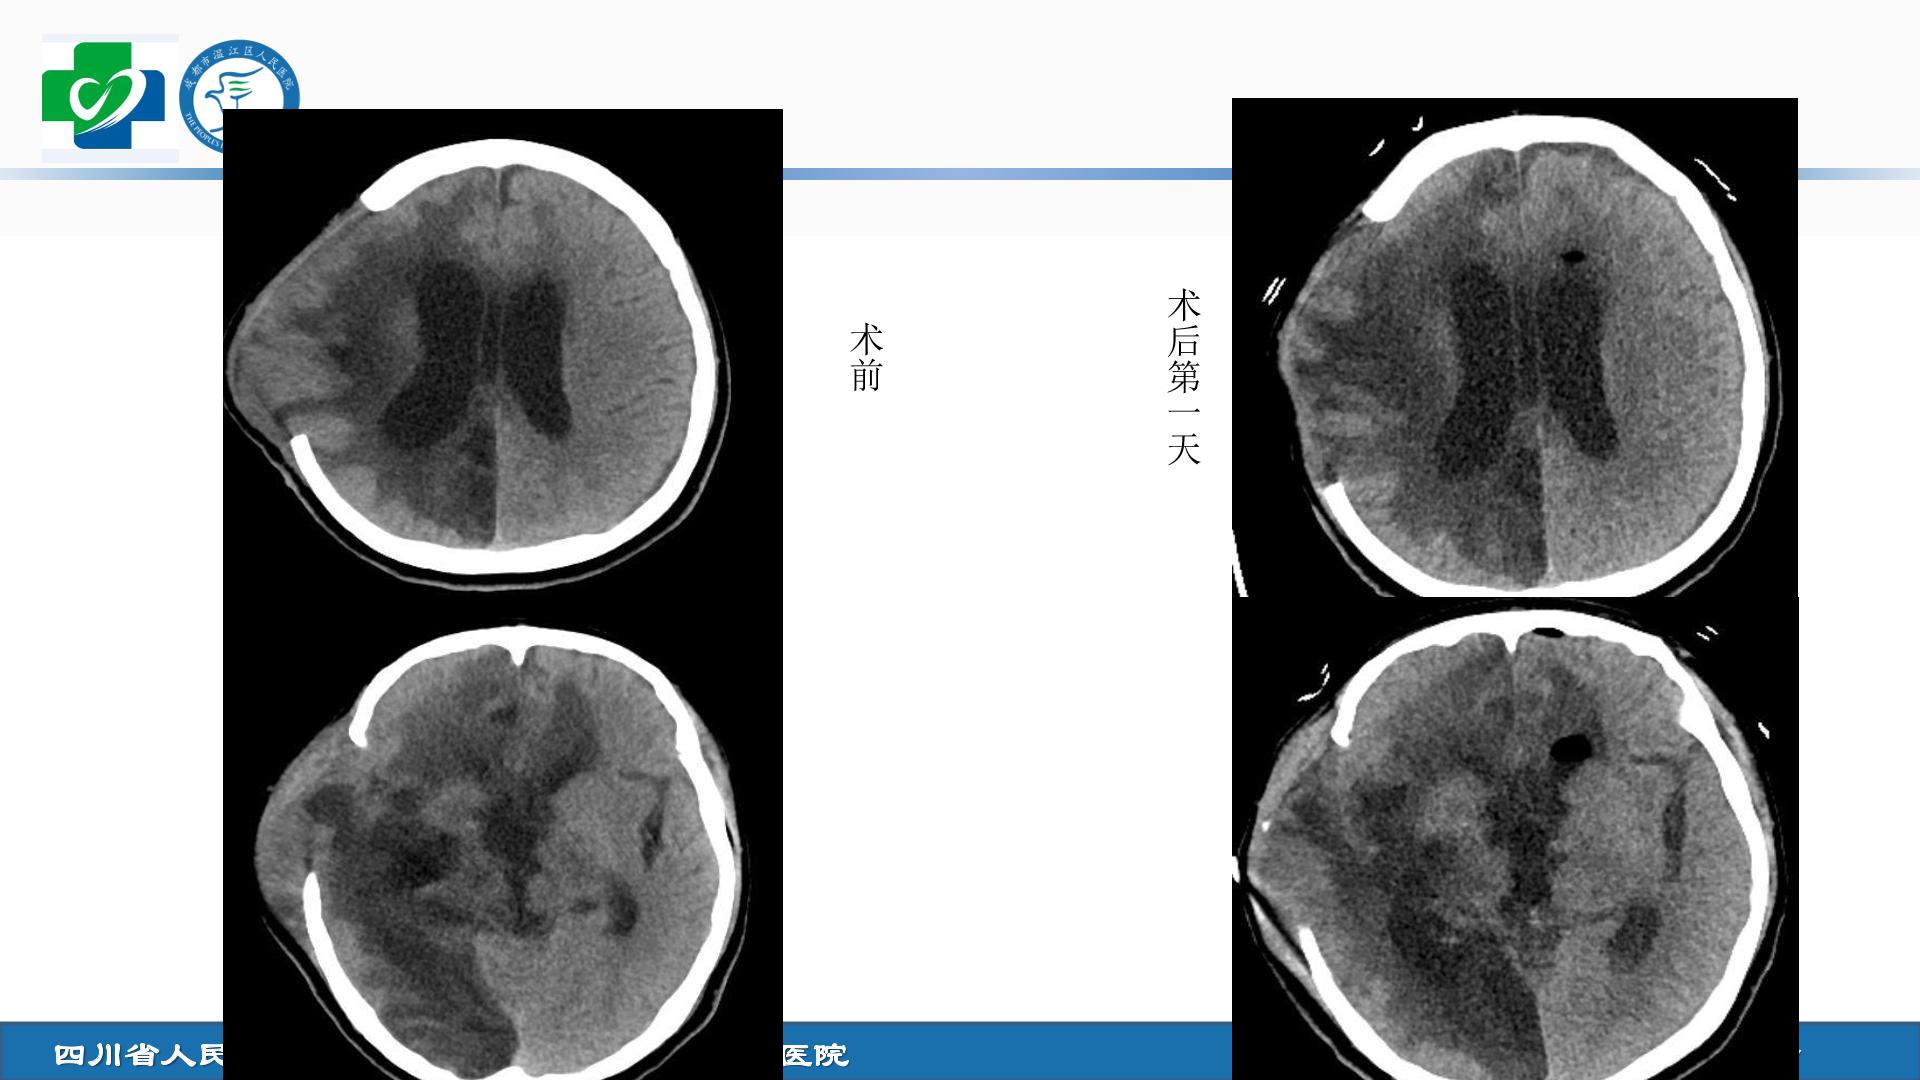

•女性,37岁,外伤后意识障碍1+月。诊断为:特重型颅脑损伤、多发脑挫裂伤。入院后急诊行右侧开颅去骨瓣减压术+血肿清除手术。术后1+月复查头颅CT发现脑室系统扩大,考虑脑积水。 •治疗方案:内镜下三脑室底造瘘手术。